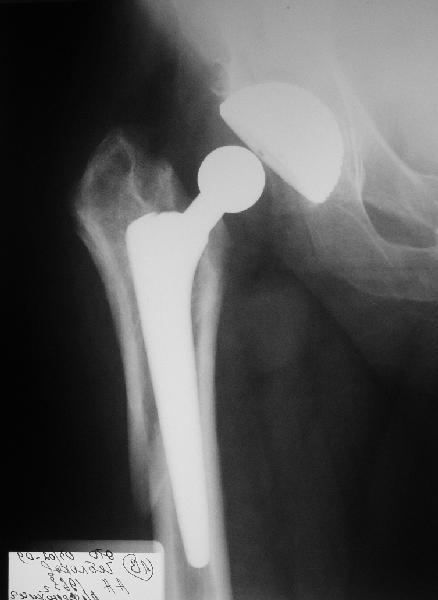

Мужчине 1963 г. бедра в октябре прошлого года в Кургане сделано

эндопротезирование правого тазобедренного сустава (последствия перелом

шейки бедра) бесцементным протезом Cerafit.

Все было благополучно, пациент уже ходил без трости, когда в начале

января 2009 упал на улице на правый бок.

Госпиталирован по месту жительства (МСЧ г. Новоуральск). Уложен на

скелетное вытяжение. На снимках от 3 февраля видно миграцию ножки в

дистальном направлении, она явно нестабильна.

В нашей больнице вряд ли что-то удастся сделать. Сопутствующих

заболеваний нет. Хотелось бы получить совет по тактике. Если нужно

ревизионное протезирование, куда лучше пациента направить?